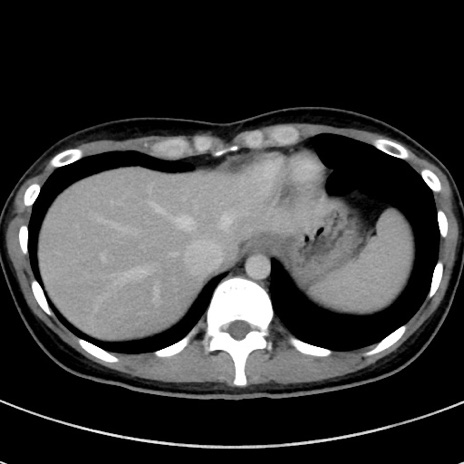

症例17(横断像)

【症例】20歳代女性

【主訴】嘔吐、下腹部痛

【現病歴】昨日夕食後に嘔吐し下腹部痛が出現。本日になっても嘔吐持続し改善しないため来院。

【身体所見】意識清明、BT 37.2℃、BP 108/67mmHg、腹部:平坦、やや硬、下腹部正中から右にかけて圧痛あり、反跳痛軽度あり、tapping pain(+)。

【データ】WBC 13600、CRP 14.94